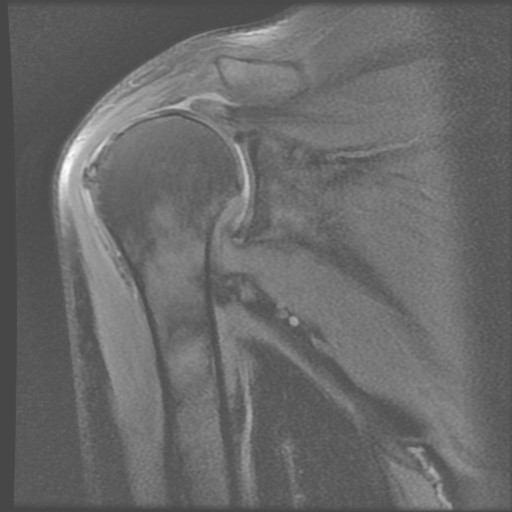

慢性巨大旋轉袖韌帶斷裂

但是對於已經斷裂一陣時間的高齡患者,常常因反覆的拉扯,使韌帶質地變差,造成脂肪性變化;另外,肌肉因持續收縮,使斷裂的距離越來越寬,造成無法將韌帶拉回正確的位置固定,使成手術失敗。

▲慢性巨大旋轉袖韌帶斷裂